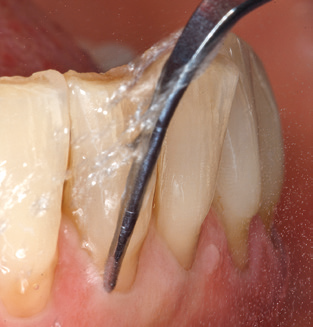

Fig. 1: Panoramic radiograph of initial situation in 2004.

A 52-year-old patient presented in our clinic for the first time in 2004 following tooth loss in the third quadrant, expressing a desire for a new prosthetic restoration. Periodontal and radiological diagnostics revealed the need for extensive periodontological treatment. In addition, teeth 48, 28 and 27 were attributed a very poor prognosis and were subsequently extracted (Fig. 1). Following the successfully completed, systematic periodontological treatment, a fixed dental implant was inserted with the introduction of five implants in tooth regions 35, 36, 37, 46 and 47. Prosthetic treatment of the natural teeth was effected with veneered zirconium dioxide ceramic crowns; the implants were composed of two-piece, individual zirconium dioxide abutments and similarly veneered crowns made of a zirconium dioxide ceramic (Cercon base colored, Dentsply Sirona Lab). Definitive insertion of the prosthetic restoration occurred in 2005.